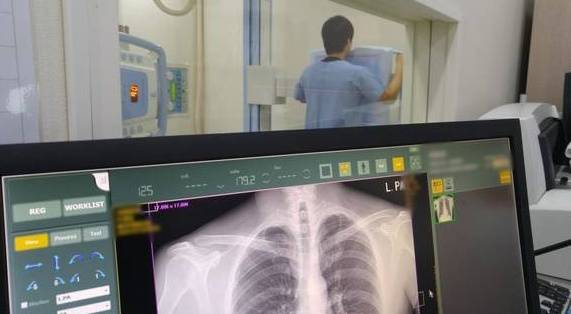

X-선검사, 흉부전산화단층촬영(CT)에서 양쪽 폐 하부에 망상 결절 모양의 섬유화가 주로 관찰된다. 병이 진행하지 않은 초기 상태에서는 정상으로 나타날 수도 있기 때문이다. 또 폐활량검사에서 폐가 뻣뻣해지면서 폐활량이 저하되는 현상을 보이거나 폐조직 검사에서 염증과 섬유화가 섞여서 나타난다. 확진을 위해서는 흉부전산화단층촬영 이외에 폐기능검사나 기관지 내시경검사, 폐조직검사 등이 필요할 수 있다.